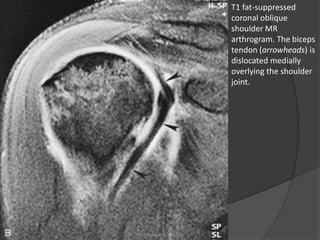

T1 fat-suppressed

coronal oblique

shoulder MR

arthrogram. The biceps

tendon (arrowheads) is

dislocated medially

overlying the shoulder

joint.

• 40.

T1 fat-suppressed coronal oblique shoulderMR arthrogram. The biceps tendon (arrowheads) is dislocated medially overlying the shoulder joint. Dr. Emanuel R. Dantas